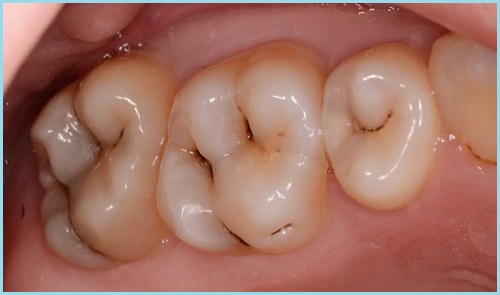

Кариес, как прогрессирующее заболевание, имеет несколько стадий своего развития. Коротко рассмотрим основные стадии: